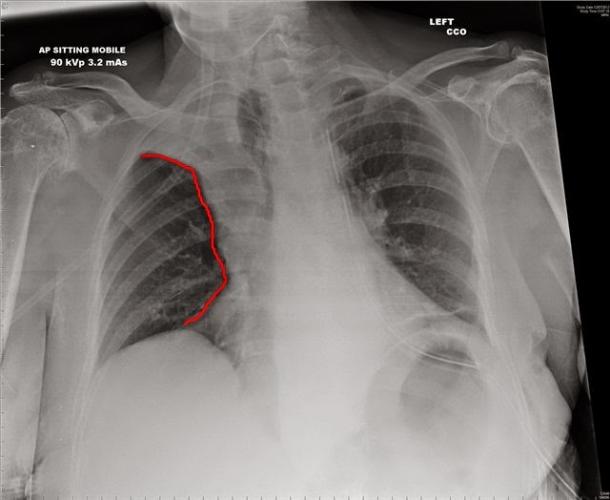

На рентгеновских снимках выявляют следующие признаки, указывающие на спадение легочной ткани:

Однородное затемнение в области поражения. Размеры тени зависят от вида ателектаза: при долевом выявляется обширное затемнение, при сегментарном — в виде клина или треугольника, расположенного вершиной к корню легкого, дольковые ателектазы множественные и похожи на очаговую пневмонию. Дистензионный ателектаз расположен низко, около диафрагмы, имеет небольшие размеры и вид поперечных полос или темных дисков. Смещение органов: при компрессионном ателектазе смещение наблюдается в здоровую сторону, так как на стороне поражения давление больше, при обтурационном, наоборот – смещение будет в сторону ателектаза, так как на стороне поражения нарастает притягивающее отрицательное давление. Подъем купола диафрагмы – это видно по расположению печени.

Помимо всего перечисленного выше, рентгеноскопия, то есть исследование «вживую», позволяет увидеть куда смещаются органы в зависимости от фазы дыхания, кашля. Это является дополнительным признаком ателектаза, помогающим выявить тип болезни.

Предварительным, рентгенологическим диагнозом является «синдром правой доли», при котором выявляется затемнение площади средней доли правого легкого.

Частое возникновение ателектаза правого легкого связано с анатомическими особенностями правого среднедолевого бронха: он узкий и длинный, поэтому часто происходит его перекрытие при патологическом процессе.